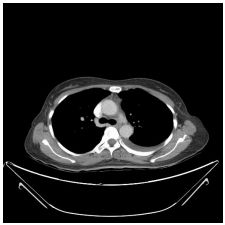

5. 57 y female, breast ca for survey